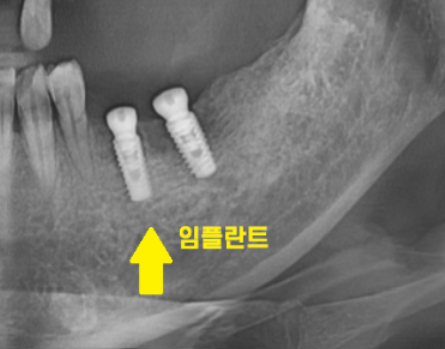

뼈가 거의 없는 경우에는

임플란트를 잇몸 안에 묻어두기도 하는데요.

이럴 경우에는 잇몸밖에 안느껴지기 때문에

임플란트 심은게 맞나.. 싶기도 합니다.

겉으로 봤을 때는 잇몸만 느껴지지만

x-ray를 보실까요~?

임플란트가 잘 심어져있습니다.